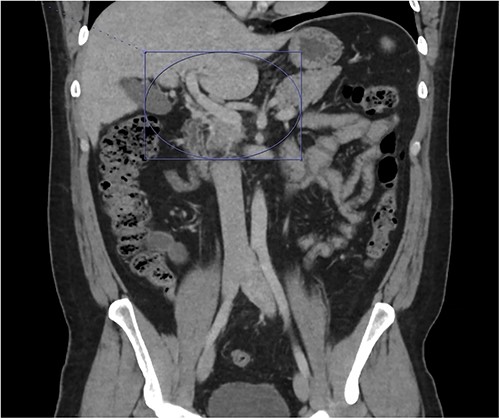

On presentation to the emergency department (ED), he was afebrile and normotensive with blood pressure in the 120s/80s though he had sinus tachycardia (heart rate 120–130 s). His abdomen was soft and diffusely tender with point tenderness at McBurney’s point and negative Rovsing’s sign. He had no signs of frank peritonitis. His complete blood count revealed leukocytosis (WBC 11K/μl), lactic acidosis (lactate 3 mmol/l), and mild transaminitis with AST 72 and ALT 101. An intravenous (IV) contrast-enhanced computed tomography scan of the abdomen/pelvis demonstrated a mildly dilated appendix (~8 mm) with surrounding fat stranding but no appendicolith, perforation, or abscess (Fig. 1). Interestingly, a partial portal vein (PV) and superior mesenteric vein (SMV) thrombosis were also noted (Fig. 2). Initial blood cultures were collected, which remained without growth.

A hyperemic and inflamed appendix can be seen without an abscess, perforation, or appendicolith.

Thrombosis can be seen extending into the mesenteric venous system as well as the intrahepatic portal veins; associated mesenteritis and abdominal ascites (not well visualized) are also seen.

Patient was admitted to the surgical service and started on broad-spectrum IV antibiotics (piperacillin–tazobactam) and was made nil per os. He was resuscitated intravenously with 2 l of crystalloid. Given the thrombosis of his PV and SMV, the patient was initiated on systemic anticoagulation with IV heparin which achieved therapeutic dosing within 24 hours. Over the course of the next few days, his abdominal pain and tachycardia improved. Interval CT abdomen/pelvis scan 5 days from presentation demonstrated progression of the thrombus to involve lobar, segmental, and subsegmental portal venous branches as well as the splenic vein distal to the portosplenic confluence (Fig. 2).